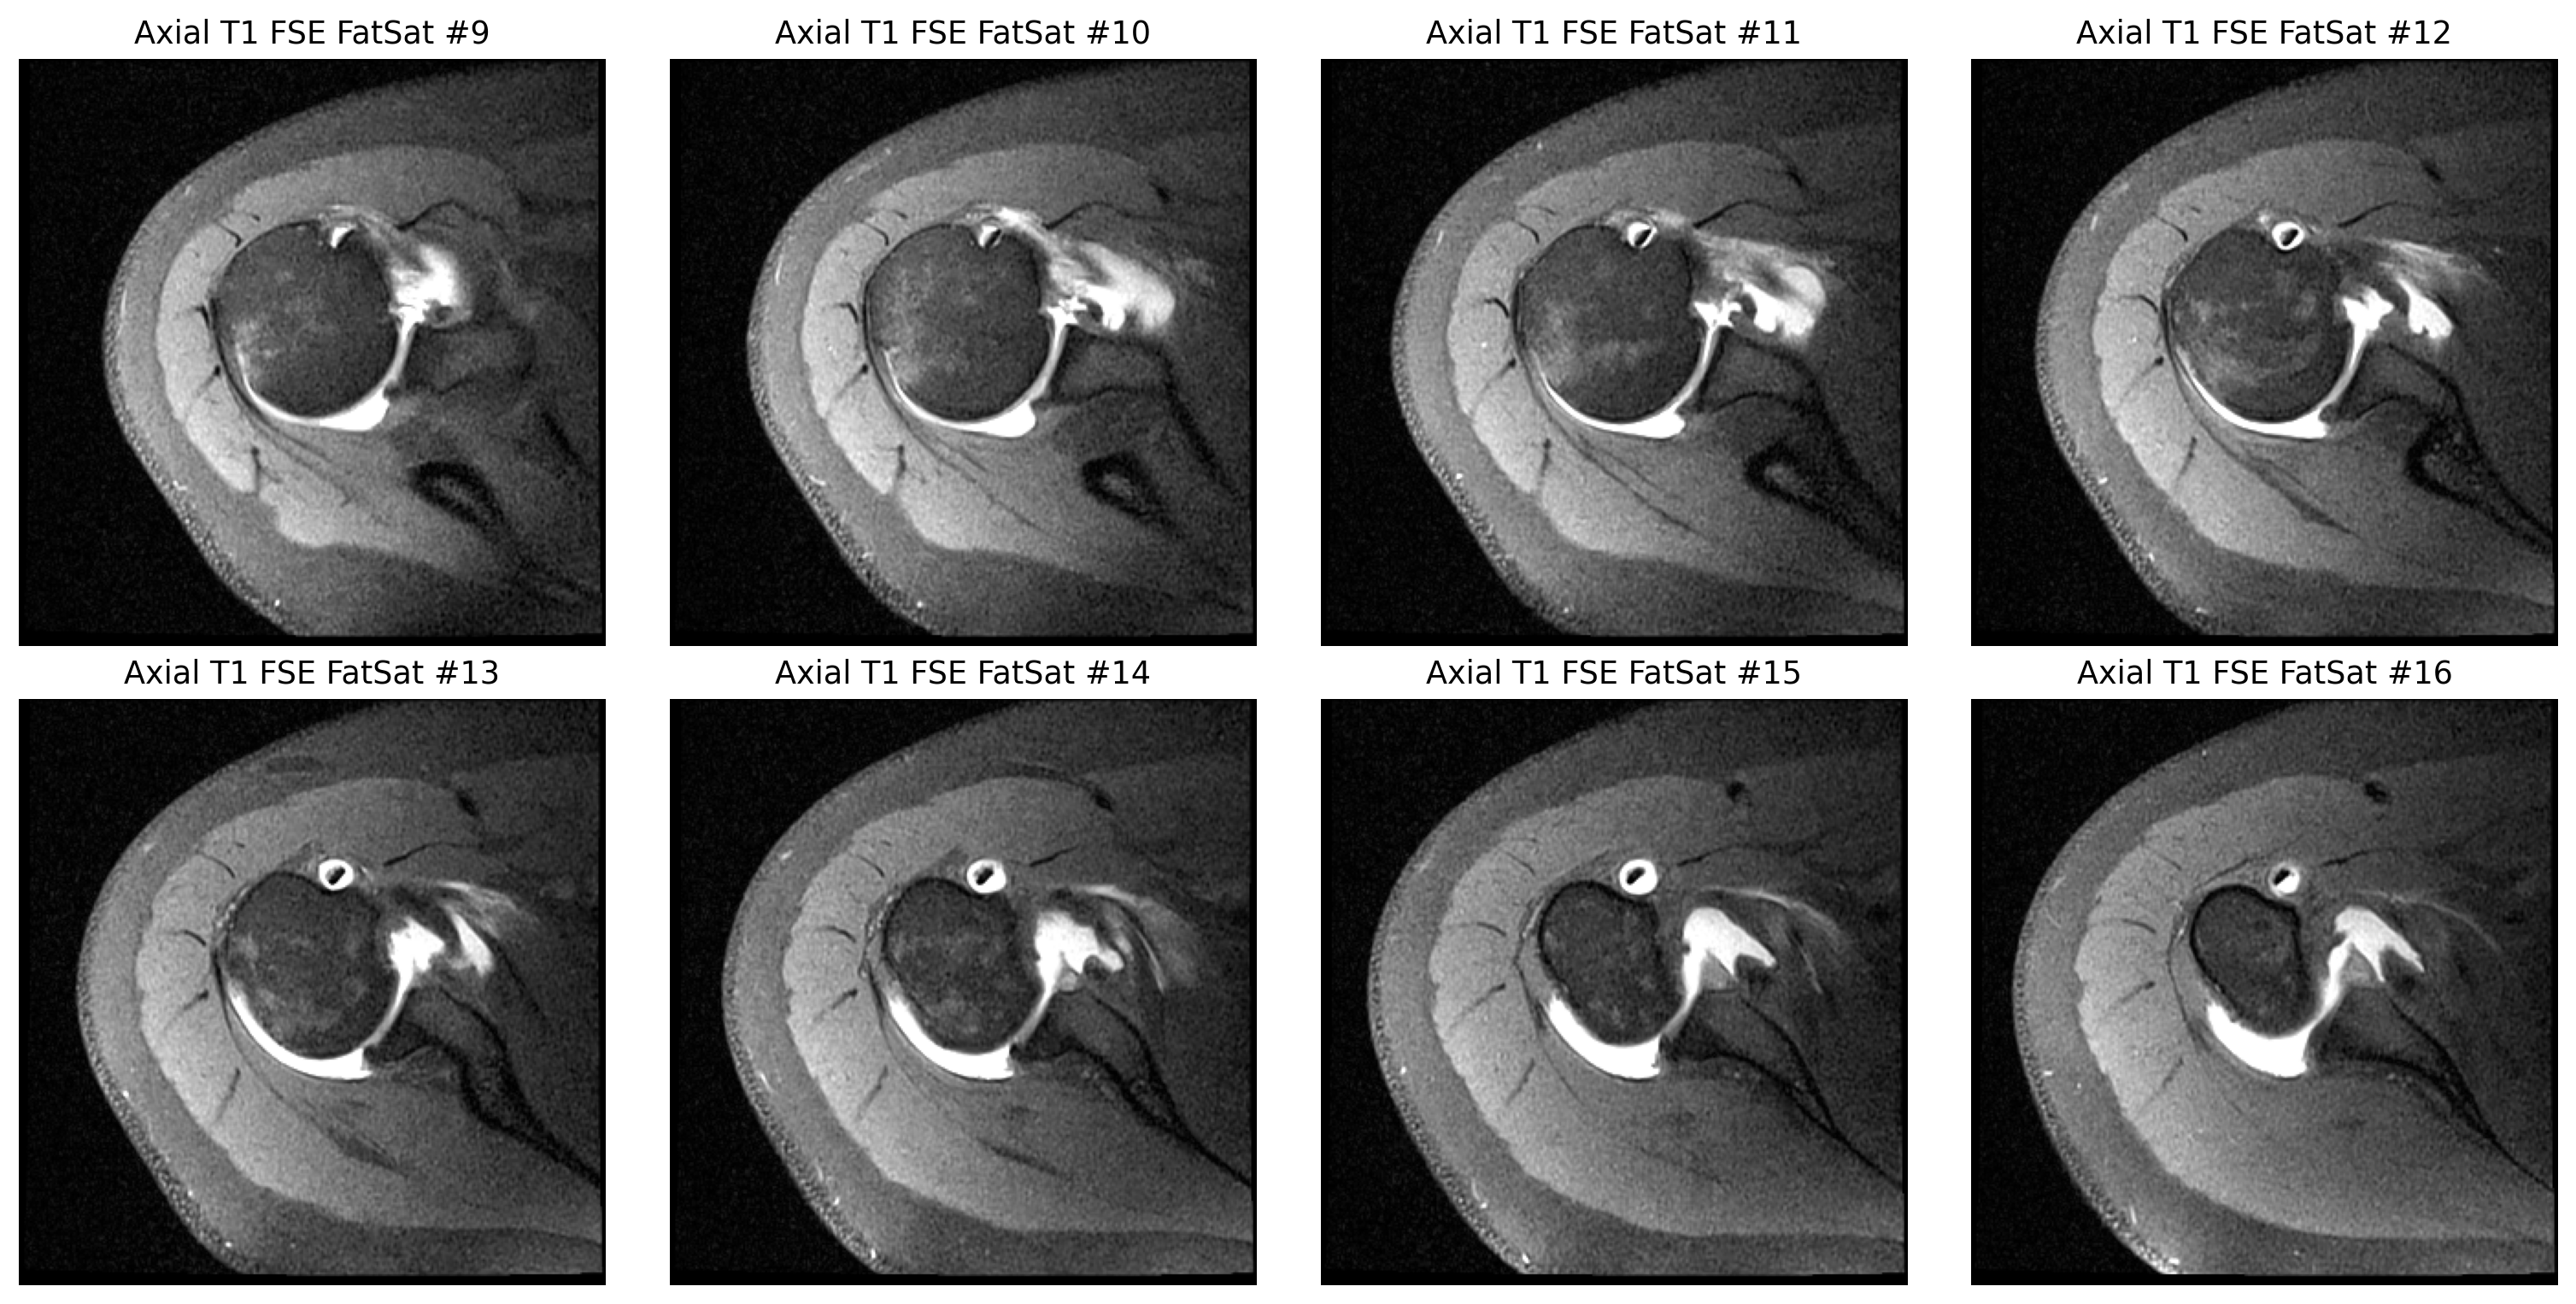

The cuff finding was checked in coronal and sagittal views, while the labrum was reviewed on axial arthrogram slices.

Whether there is a definite labral tear

I would not claim either one as certain from these exported images without a full diagnostic viewer and radiologist review.